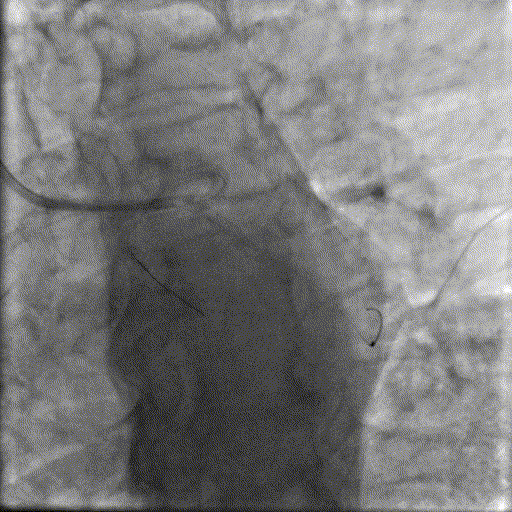

基础造影

右冠状动脉近中段可见支架影,支架通畅无狭窄,右冠状动脉远段狭窄50%;前降支近中段弥漫性重度钙化伴成角,近段狭窄80%,中段狭窄90%,第一对角支近段狭窄70%;回旋支近段狭窄70%,第一钝缘支狭窄90%。

手术经过

OM优先处理:

球囊预扩

用预扩张球囊对OM病变部位行预扩张。

支架植入并后扩

于LCX中段至OM支植入一枚药物洗脱支架,经非顺应性球囊后扩张支架,复查造影提示支架贴壁良好,无夹层撕裂。

LAD处理:

用预扩球囊扩张LAD病变,支架无法通过。为了解血管病变分布情况及钙化程度,遂启用IVUS检查。

术前腔内影像学IVUS指导

IVUS提示LAD近中段钙化病变,中段可见360°环形钙化。

冲击波球囊治疗

3.0x12@4atm 冠脉血管内冲击波导管顺利推送至前降支近端,但无法通过成角钙化处,故于血管近端就地进行10个周期治疗,复查造影见近端狭窄明显减轻;再次选择2.5x12@4atm冠脉血管内冲击波导管推送至成角钙化处,逐步掘进扩张病变并给予冲击波治疗,最终顺利通过成角钙化处,并于前降支中段再次进行10个周期的冲击波治疗。

于LAD近中段串联植入两枚药物洗脱支架,经非顺应性球囊后扩张支架,复查造影及IVUS提示支架膨胀完全,贴壁良好,无夹层撕裂。

LCX处理:

于LCX近段与原支架串联植人一枚药物洗脱支架,经非顺应性球囊后扩张支架,复查造影&IVUS提示支架贴壁良好,无夹层撕裂。

最终,经FFR检测,结果达0.96,提示冠状动脉功能学恢复满意,达到预期治疗目标,故本次介入治疗操作圆满结束。